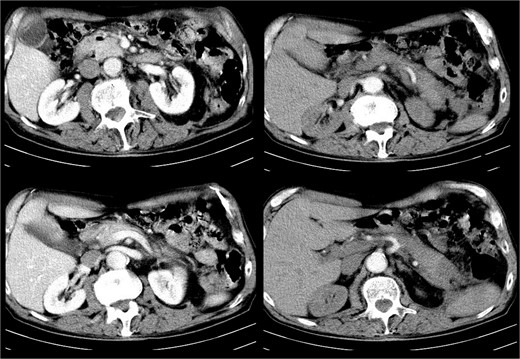

A subsequent microbiological examination showed no bacterial growth. Normal laboratory findings. Additional abdominal ultrasound and CT showed no significant remaining fluid collections (Fig. 2).